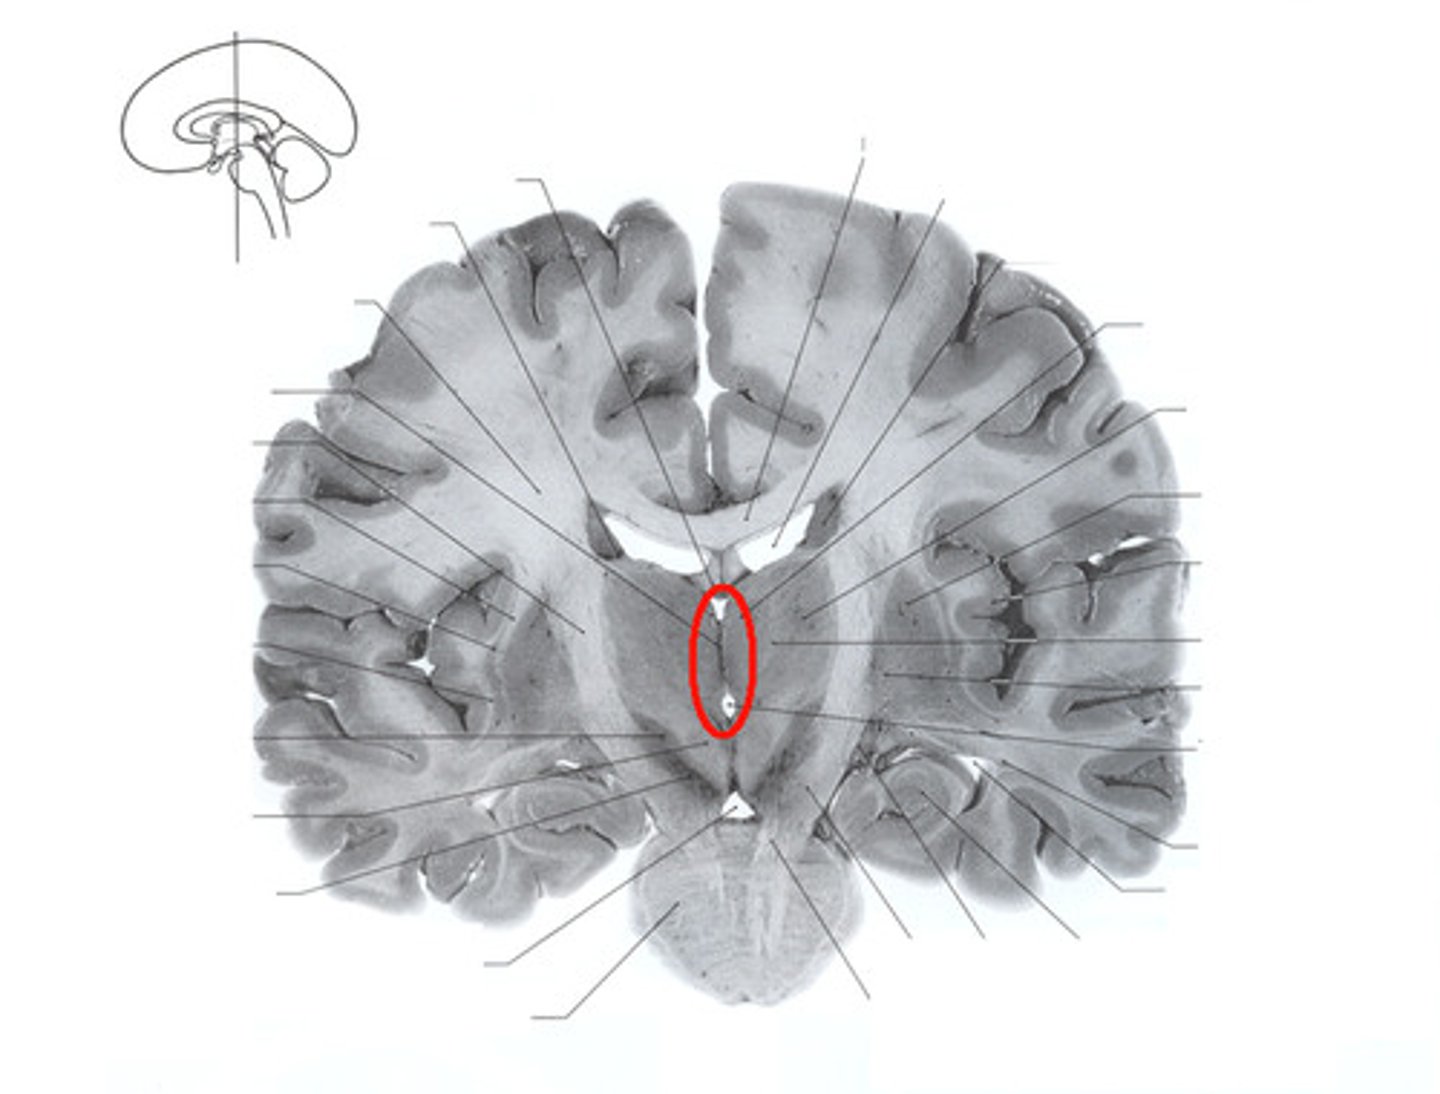

Lateral Ventricle

Located in each hemisphere of the cerebrum, C shaped located in the hemisphere of the cerebrum and contains CSF.